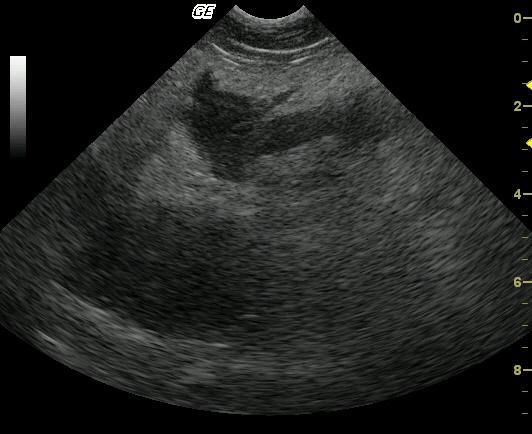

This 6-year-old Maltese presented for diarrhea, poor appetite, and lethargy immediately prior to the sonogram with a history of acute vomiting 2 weeks prior that had resolved without intervention. The patient also presented concurrently with acute anal sacculitis and dermal hot spots. Outpatient therapy with antibiotics proved mildly effective. CBC and blood chemistry analysis demonstrated a normal complete blood count and moderately elevated amylase, moderately elevated lipase, and moderately elevated SAP. Mild hypoalbuminemia was also present initially. A second analysis revealed similar values regarding amylase, lipase, and SAP with new moderately elevated cholesterol and moderately elevated triglycerides and moderate hypoalbuminemia.